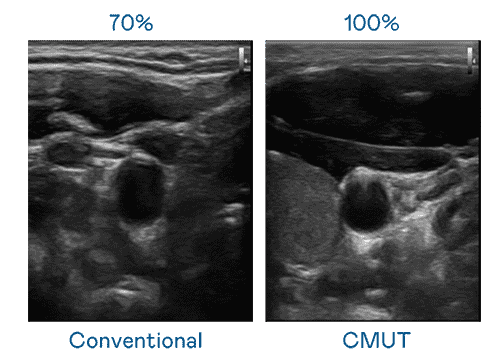

CMUT 技术是一种用电容式微机电元件来产生超音波讯号的技术。。。与传统 PZT 压电式技术相比,,,CMUT 频宽增加 30%,,更宽频的超音波讯号让影像解析度大幅提升,,是实现高影像品质医疗超音波扫描、、、促进精准医疗发展的关键技术。。

超音波影像的解析度高低,,,,首先取决于探头能发出的讯号频宽。。。z6尊龙 CMUT 可提供高清晰的超音波讯号,,,,提供高频宽、、高灵敏度、、、、影像纹理细节更高的超音波影像,,,协助医护人员缩短影像判读时间及利用精准的医疗影像进行诊断。。。